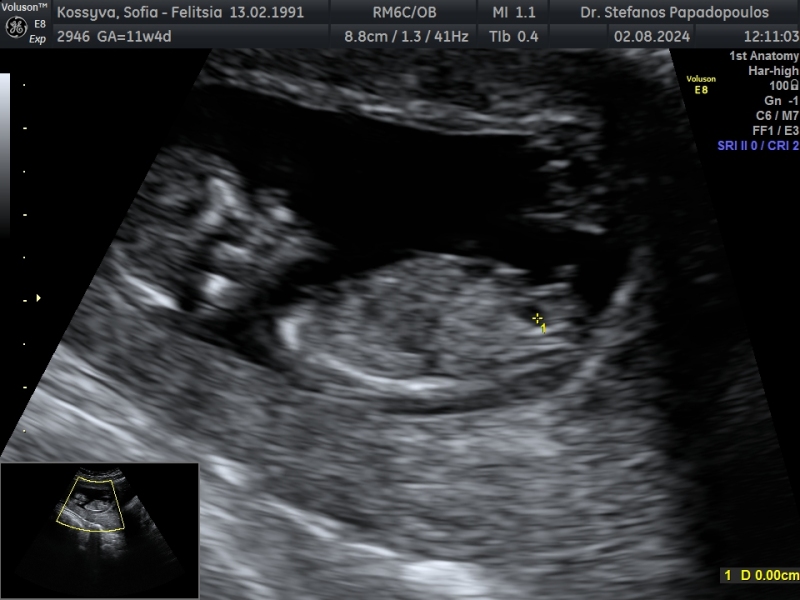

Hello, yesterday i have an ultrasound and im 12 weeks 5 days!!! I would like to ask you your opinion about the gender ! Thank you in advance ❤️

I’m really bad at that game but you may want to delete and repost seeing as the picture contains all your personal information.

Yeah the photo shows your name and your DOB etc OP. I think girl, for what it's worth, but yes delete or edit if possible for your own confidentiality.

❤️ thank you !! I hope for

a little girl ! Because if you see the scan I rhink

that the nub is stalked and I think that its

a male trait development